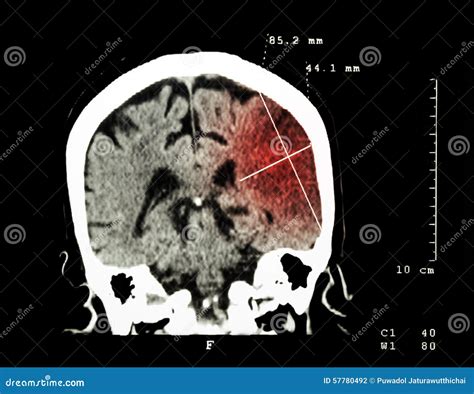

Interpreting Ischemic Stroke CT Results

Interpreting the results of an Ischemic Stroke CT scan requires expertise and experience. Radiologists and neurologists work together to analyze the images and make a diagnosis. Key findings that may be observed include:

• Early ischemic changes: These can appear as areas of low density (hypodensity) in the brain tissue, indicating reduced blood flow.

• Hyperdense artery sign: This is a bright appearance of an artery on a non-contrast CT scan, suggesting the presence of a blood clot.

• Mass effect: Swelling or compression of brain tissue due to the stroke, which can be seen as a shift in the midline structures of the brain.

These findings help healthcare professionals determine the type and severity of the stroke, as well as the appropriate treatment plan.

• Case 1: Early Detection: A 65-year-old patient presented with sudden weakness on the left side of the body and difficulty speaking. An Ischemic Stroke CT scan revealed a blood clot in the right middle cerebral artery. Thrombolytic therapy was administered within the critical time window, leading to a full recovery.

• Case 2: Complex Diagnosis: A 50-year-old patient with a history of atrial fibrillation experienced a sudden onset of vision problems and dizziness. A CT scan showed early ischemic changes in the brainstem. Further imaging with CTA and CTP confirmed the presence of a blood clot and guided the decision for mechanical thrombectomy.